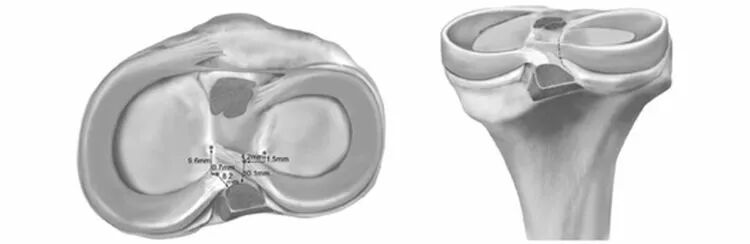

半月板とは? 半月板は、膝の関節を体重や衝撃から守り、安定させる役割をしています。 損傷の程度やタイプによって対処法が変わってきます。 分類 ・縦断裂 ・横断裂 ・水平断裂 ・フラップ状断裂 ・バケツ柄状断裂右:外側半月板水平断裂 左:縦断裂(バケツ柄状断裂) 右:切れた根本部分 半月板縫合術 半月板の周辺1025%には血行があるので治癒する可能性があることから、半月板辺縁断裂に対しては半月板縫合術が行われます。2-4週間のギプス固定が必要になります。本法の適応は若年者で比較的 半月板水平断裂にprpfdは効果的ですか? top ひざ関節痛q&a 半月板水平断裂にprpfdは効果的ですか? 1年程前に左膝内側半月板水平断裂と診断されました。 症状は波があり、基本的に正座は出来ず、疲れてくると階段をのぼる際に鋭い痛みが出たり、歩く際に膝の前方まで痛みが出ます

その中のひとつが半月板の断裂形態です。 関節のmriを紐解くと、半月損傷は下記のごとく分類されます。 水平断裂 縦断裂 ① 水平断裂 ①の水平断裂は下図のような断裂形態で、内側半月の後節に好発します。変形性膝関節症に伴う例が多く、外傷性では>解説 : 半月板断裂は水平断裂と垂直断裂に大別されるが。広範囲に縦断裂が生じ、その一方がバケツの柄のように翻転したものをバケツ柄断裂と呼ぶ。矢状断像では この内方に偏位したバケツの柄部分が後十字靭帯( PCL )と併走し、 double PCL sign を示す。本例では大腿骨外顆と脛骨外顆